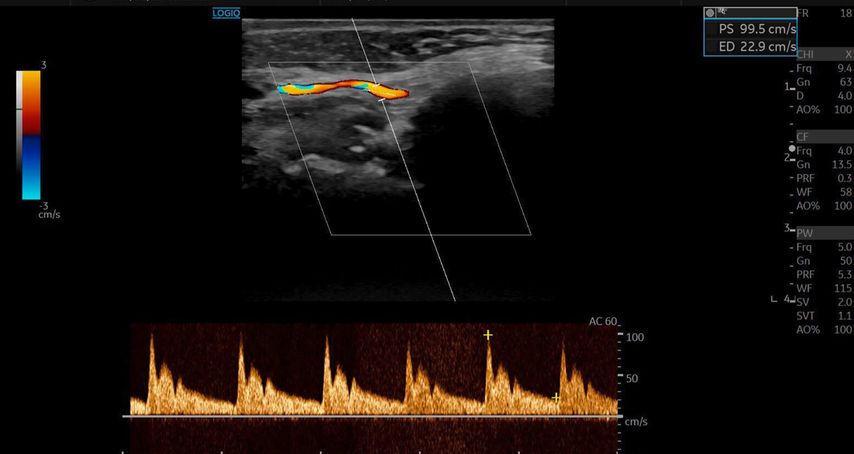

Die Duplexsonografie ergab folgende Befunde (Abb. 5 und Abb. 6):

Der Durchmesser der A. angularis und A. facialis hatte sich nahezu verdoppelt.

Die systolische Spitzengeschwindigkeit (PSV) stieg von 20cm/s auf über 100cm/s.

Die enddiastolische Geschwindigkeit (EDV) betrug nun 20cm/s, was auf eine periphere Vasodilatation und eine Wiederherstellung der Makrozirkulation hindeutete (Abb. 7).